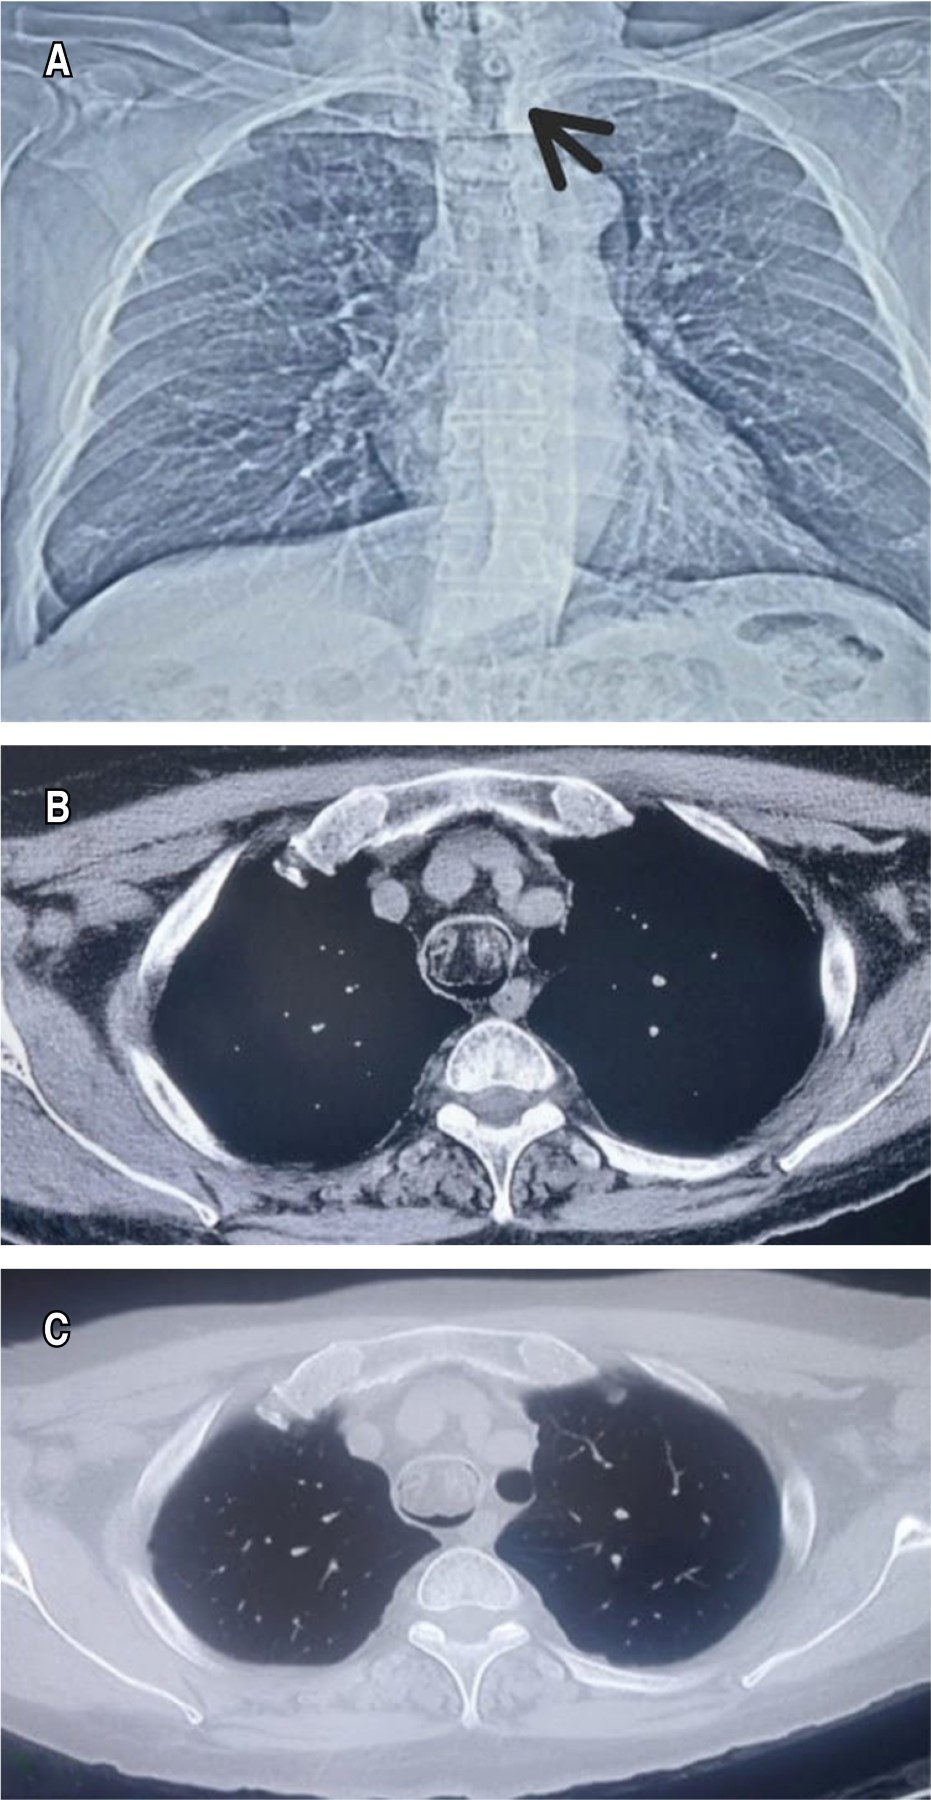

Hombre de 70 años, con cuadro clínico de seis meses de evolución, caracterizado por disnea de medianos esfuerzos, que progresa a pequeños esfuerzos y tos productiva, con expectoración hialina, no cianosante, ni disneizante. Durante la exploración física, signos vitales: tensión arterial (TA) 113/101 mmHg, FC 79 lpm, FR 22 rpm, temperatura 36.2 °C, saturación de oxígeno 91% aire ambiente, gasometría arterial inicial pH 7.45, PCO2 36.7 mmHg, PO2 65 mmHg, con estridor, sin datos de dificultad respiratoria, en campos pulmonares se auscultaron estertores bilaterales. Se colocó oxígeno por puntas nasales a dos litros con saturación de oxígeno a 94%. Se realizó radiografía de tórax sin alteraciones parenquimatosas, con imagen de estenosis traqueal (Figura 1A). Se solicitó tomografía simple de tórax, con lesión irregular encapsulada adherida a pared anterolateral del tercio medio de tráquea (Figuras 1By 1C). Se realizó fibrobroncoscopia (Figura 2A), se identificó tumor blanquecino de 3 × 2 cm a nivel del sexto anillo traqueal que obstruye 95% su luz traqueal pediculado en pared anterior. Se realiza resección mediante broncoscopia rígida y resección total del tumor (Figura 2B). El examen histopatológico reportó lipoma traqueal (Figuras 2C y 2D). El paciente presentó buena evolución sin datos de compromiso respiratorio. Se egresó por mejoría, con seguimiento tomográfico al mes del procedimiento sin evidencia de recurrencia, con adecuada permeabilidad de la luz traqueal.

Comúnmente, es difícil encontrar una lesión en una radiografía de tórax convencional porque la tráquea está cubierta por el mediastino, casi siempre se observa normal, como en este caso (Figura 1).1-3 Estudios como la tomografía y la broncoscopia flexible son valiosos para el diagnóstico, mismos que fueron realizados en nuestro caso.1-3